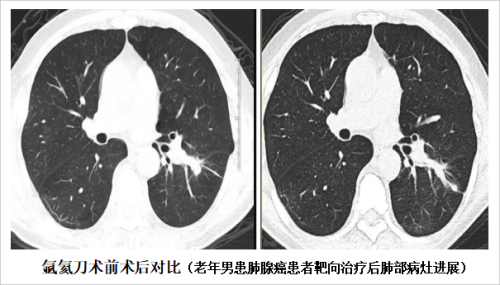

氩氦冷冻消融技术,简称“氩氦刀”,是在CT、B超等影像学设备的引导下,是全程监控精确定位微创治疗癌症的最新高科技设备系统,可连续、实时监控刀尖温度。氩氦刀是航天制导技术,也就是氩气的冷隔绝技术应用到医疗领域的结晶。